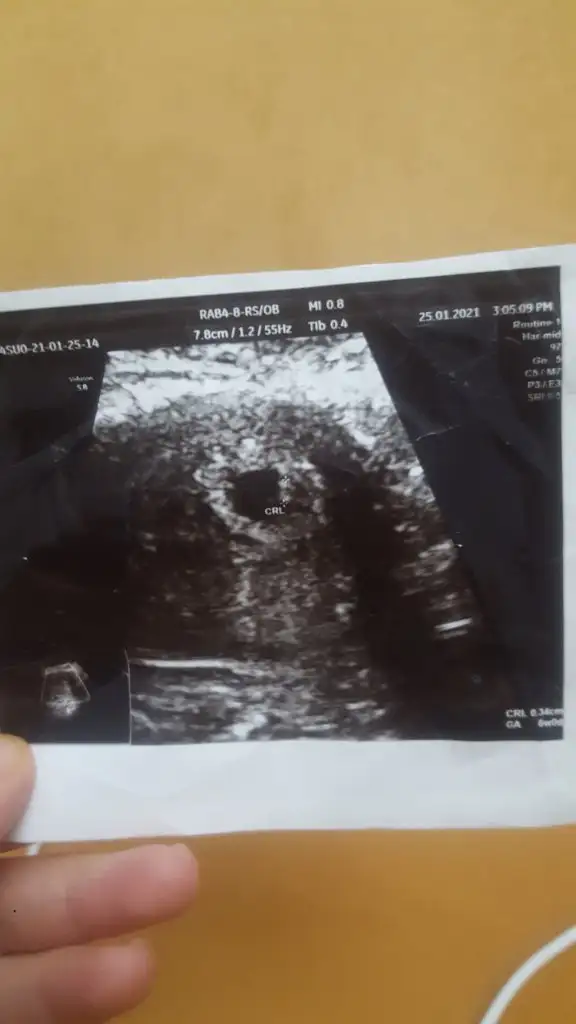

Kızlar tek tek yazamadım çok şükür kalp atışını duyduk bugün ama uygulamaya göre 6+5 olması lazım Ama ultrasonda 6+0 çıktı bı aklımı karıştırdı biraz. Birde resin ekleyeceğim bir tahminde ben alabilir miyim ?

• 16115924661521081927924.webp

16,1 KB · Görüntüleme: 64

Bi yorum da ben istiyeyim sizden çok belli belirsiz ama belki tahminleriniz olur ortada duruyor benim bebiş

Canım bence erkek hem sola yatkın duruyor hemde plasentası sağda gibi geldi bana B bitkiselhayat ın da dediği gibi kese fasulye gibi oluncada erkek derler hayırlı sağlıklı olsun inşallah❤